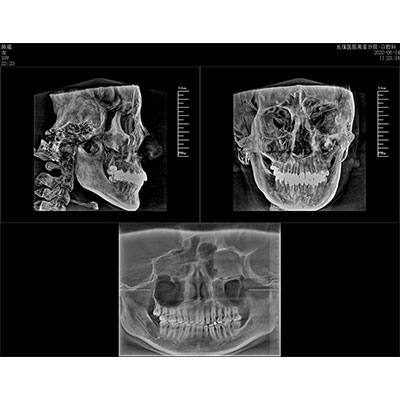

高清口腔三維CT/全景影像 PLX3000A

該款牙科CBCT產(chǎn)品采用動態(tài)平板探測器,獲得三維圖像的同時(shí)還具有數(shù)字化全景功能,廣泛應(yīng)用于口腔頜面外科、正畸科、正頜外科、種植科、牙體科、顳下頜關(guān)節(jié)科等術(shù)前術(shù)后。

專有三維重建算法,可提供任意位置高清斷層影像。

通過三維容積影像,提取高清口腔全景影像。

可同時(shí)觀察軸向面、冠狀面和矢狀面圖像,方便臨床診斷。